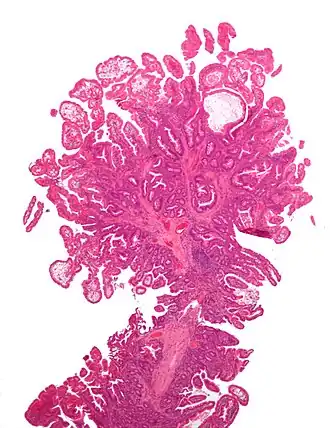

El síndrome de Peutz-Jeghers es una enfermedad autosómica dominante, se caracteriza por la producción y la presencia de pigmentaciones epidérmicas, además de la presencia de hamartomas gastrointestinales; este hecho fue confirmado en 1987 por Giardello, el cual reportó 31 casos de síndrome de Peutz-Jeghers, con daño gastrointestinal asociado a hamartomas.[1]

Generalmente la presencia de estos síntomas como los hamartomas no se considera perjudicial o maligna, pero, en el síndrome de Peutz-Jeghers varios autores han reportado casos con excesivo daño gastrointestinal. La presencia de las pigmentaciones suele ocurrir por el desplazamiento epitelial debajo de la capa muscular.[1]